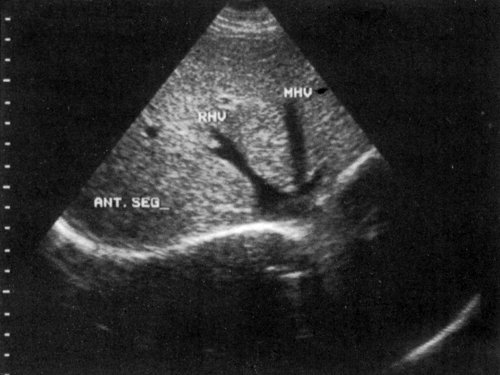

Сегментарное строение печени

Сегментарное строение печени — важная часть ультразвукового исследования, поскольку информация о том, в каком сегменте органа располагается поражение имеет большое значение. Печень может быть разделена печеночными венами следующим образом: правая вена делит правую долю на два сегмента — задний и передний (рис. 10) и левая вена разделяет левую долю на латеральный и медиальный сегменты (рис. 11). Теперь, если мы проведем продольные плоскости через левую, среднюю и правую главные воротные вены (рис. 12), то печень будет разделена на восемь сегментов (рис. 13).

Рис. 10. Подреберный косой срез через правую долю печени позволяет увидеть передний и задний сегменты (эхограмма).

RHV — правая печеночная вена, MHV — средняя печеночная вена, LHV — левая печеночная вена, RPV — правая главная воротная вена, LPV — левая главная воротная вена.

Рис. 13. Печень разделена на восемь сегментов следующим образом: 1 — хвостатая доля, которая ограничена сзади нижней полой веной и спереди главной печеночной бороздой; 2 и 3 — левый латеральный сегмент; 4 — левый медиальный сегмент; 5 и 8 — правый передний сегмент; 6 и 7 — правый задний сегмент.